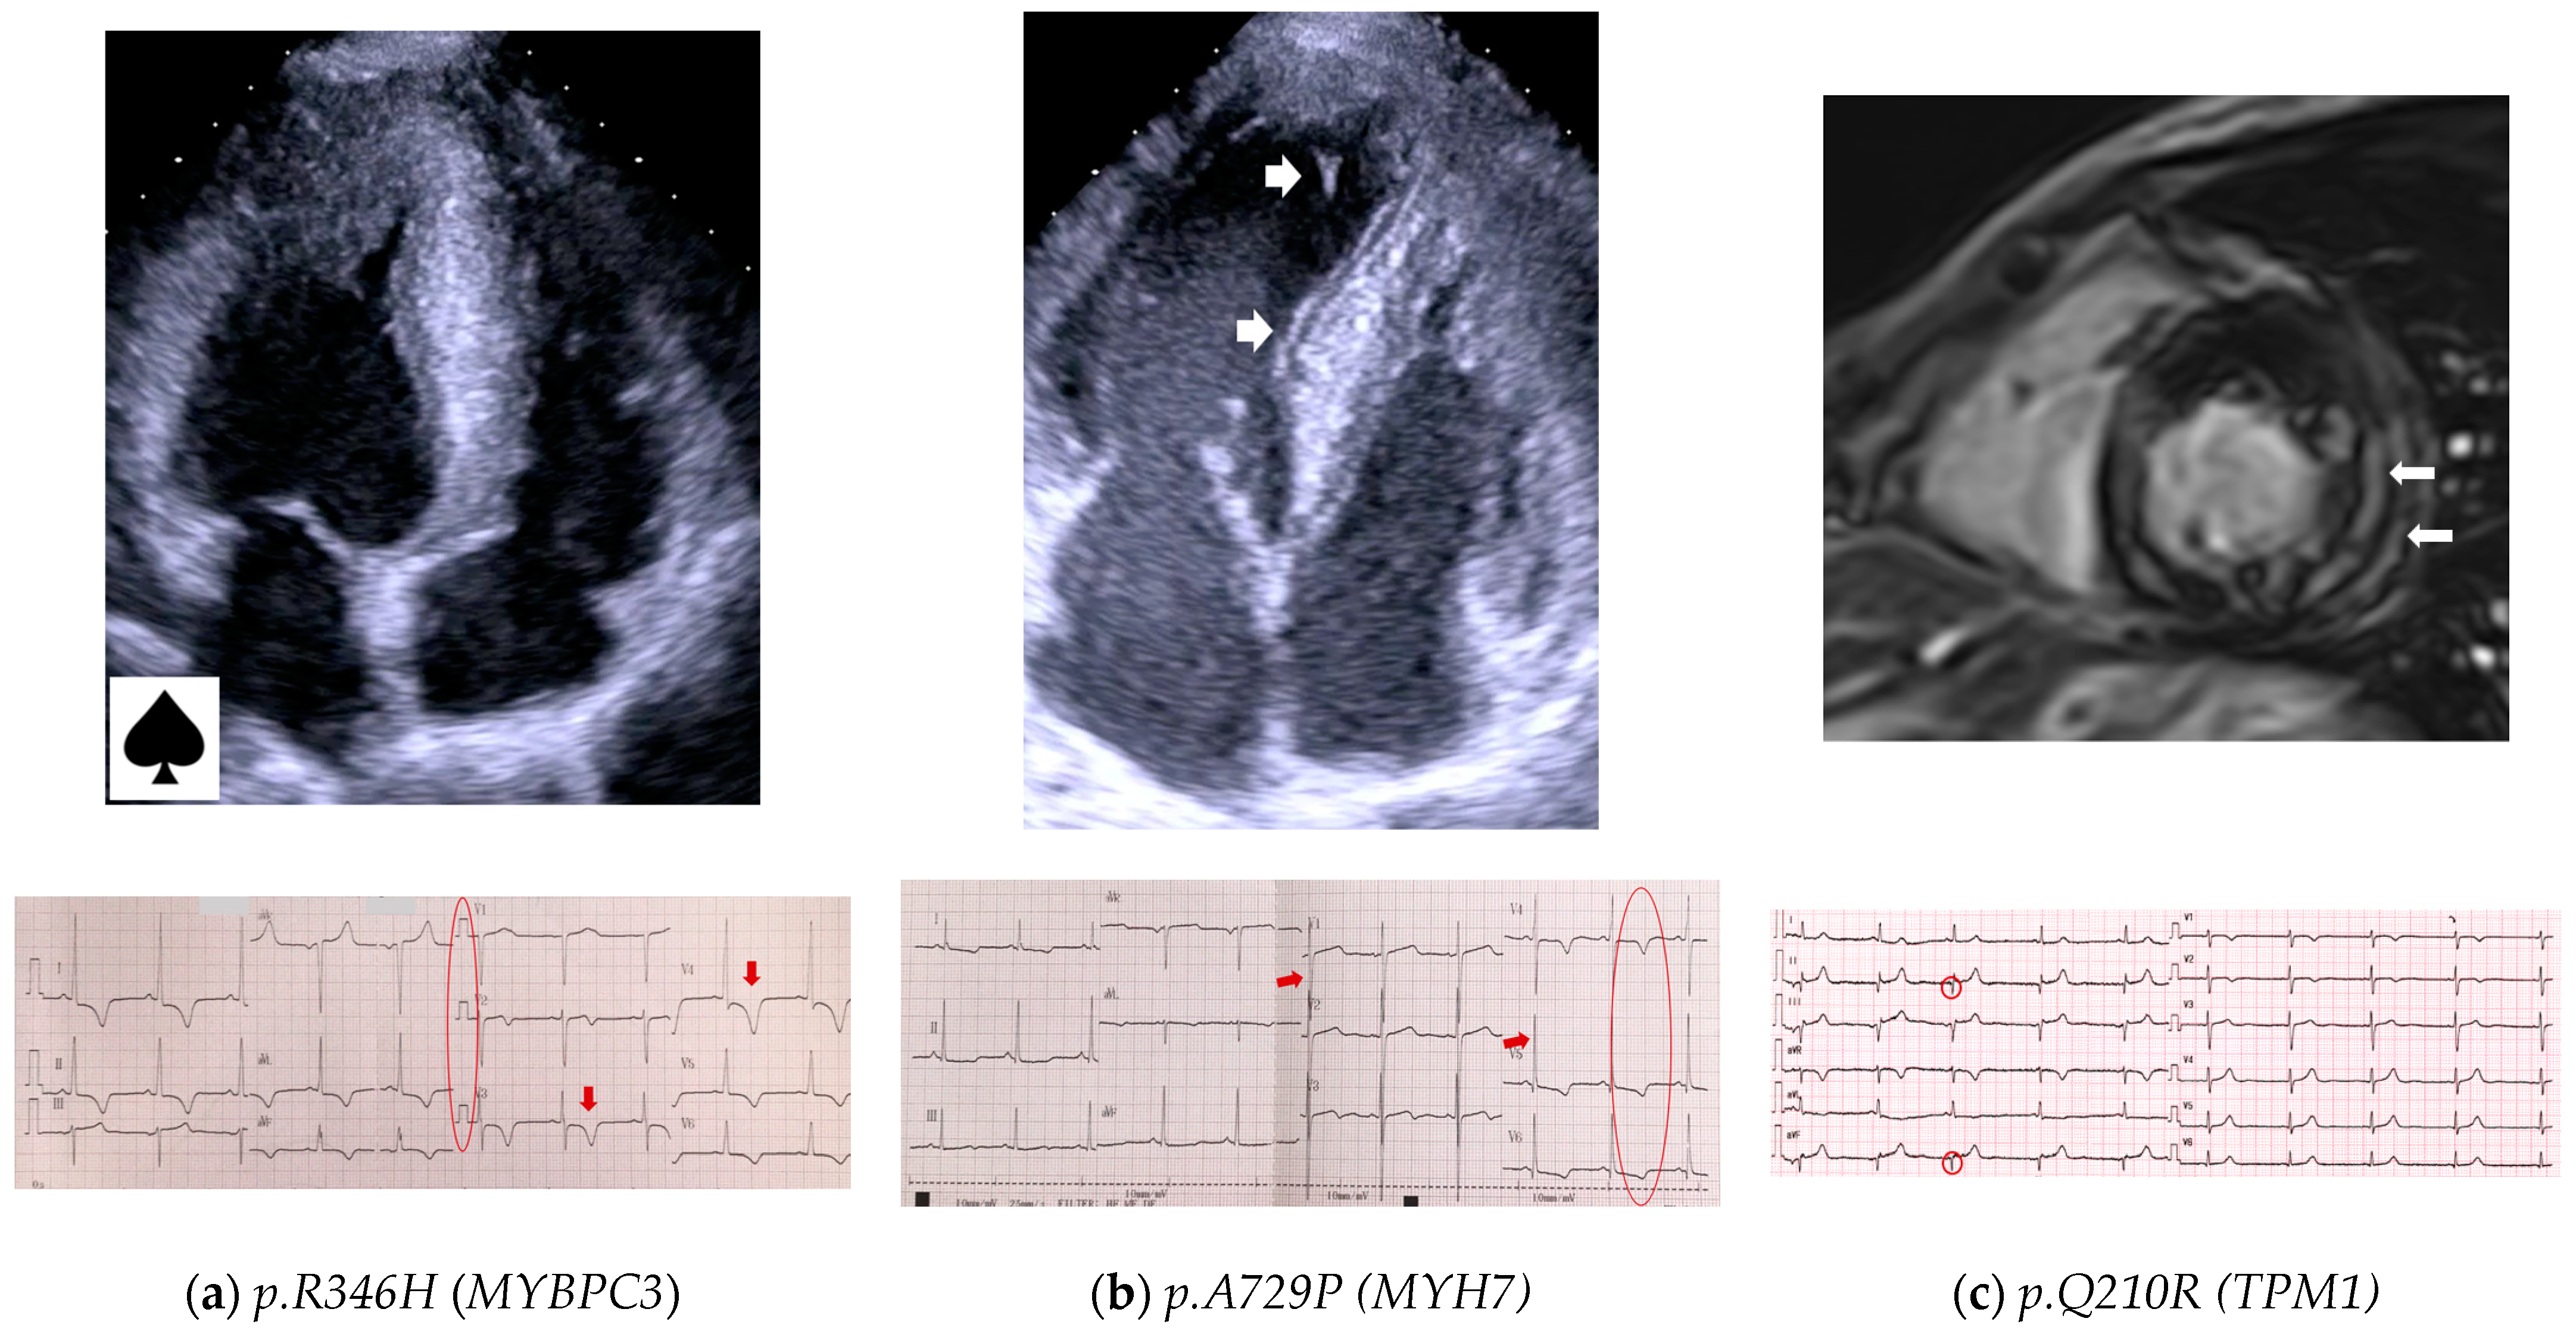

3.4.3. Genotype–Phenotype Correlations

- MYBPC3 a nd MYH7

- Thin filament of sarcomere